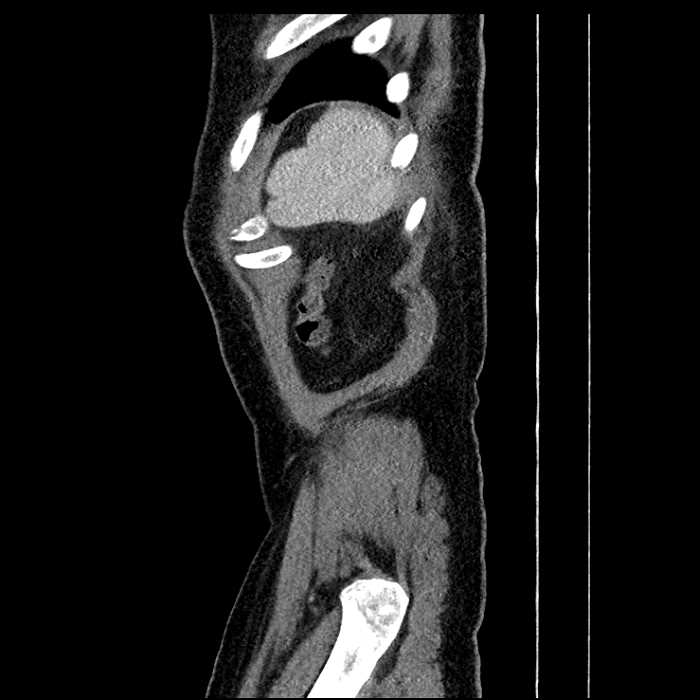

• Large fluid density structure in hepatic segments 7 and 8 measuring 10 x 7 x 7 cm with internal septation and circumferential ill-defined low density compatible with edema

• Peripherally enhancing subcapsular collections along the anterior margin of the left hepatic lobe measuring 3 x 1 cm and 2 x 1 cm

• Clearly marginated fluid density structure in segment 7 and several other scattered tiny hypodensities, which likely represent cysts

Acute sigmoid diverticulitis complicated by a small contained perforation and a large abscess in the right hepatic lobe. Additional small subcapsular abscesses along the anterior margin of the left hepatic lobe.

• The classic CT imaging appearance is a double target sign with internal low density surrounded by an internal enhancing rim (capsule) and a low density external rim (edema)

Hepatic abscess showing the double target sign with low density internally surrounded by a thin inner enhancing rim (red arrow) and ill-defined outer low density rim (yellow arrow). Blue arrow indicates an internal septation. Red arrows: additional smaller subcapsular abscesses. Red arrow: focal contained perforation associated with diverticulitis.